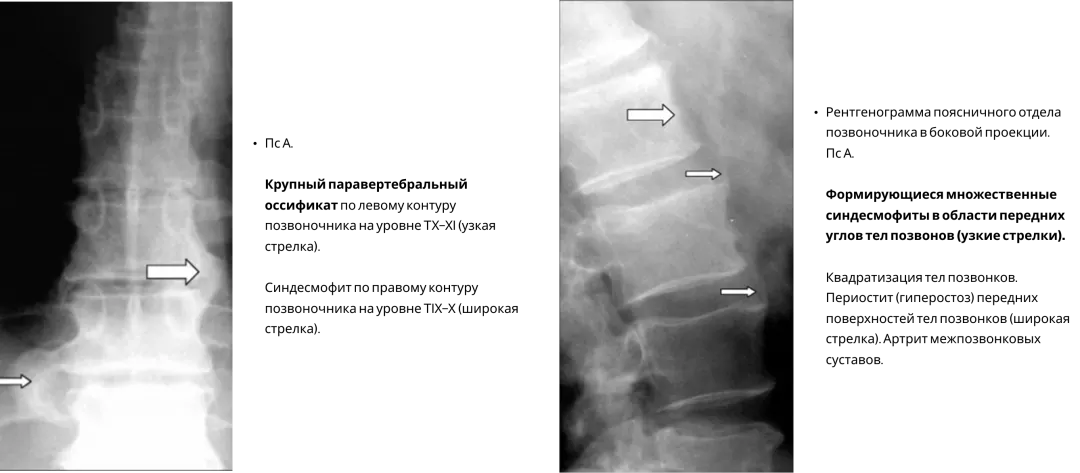

Поражения осевого скелета при ПсА имеют свои особенности3.

Асимметричные синдесмофиты, часто малочисленны, имеют больший размер и объемную форму.

Image

Frame 24061581.png

Характерными для ПсА являются паравертебральные оссификаты (см. рис.). Они имеют вытянутую форму, расположены в мягких тканях вдоль оси позвоночника, по одной из латеральных поверхностей тел позвонков и межпозвонковых дисков. В начальной стадии они не связаны костным основанием с телами позвонков. В более поздние сроки оссификаты соединяются с телами позвонков в местах прикрепления передней продольной связки позвоночника.

Frame 24061578 (2).png